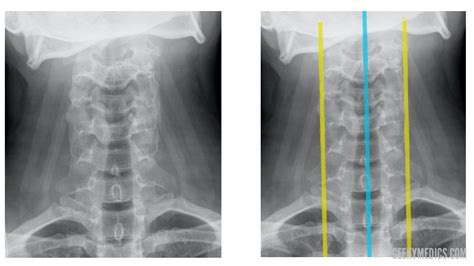

Dealing with persistent discomfort in your spine can be an overwhelming experience, leading many people to seek professional medical imaging. A back X-ray is often the first diagnostic step physicians recommend when assessing structural issues, injuries, or chronic pain in the vertebral column. By using a small dose of ionizing radiation, this imaging technique produces detailed pictures of the bones, allowing doctors to visualize the alignment, density, and integrity of your spine. Whether you are dealing with a sports injury, potential scoliosis, or long-term degenerative conditions, understanding what to expect during this procedure can significantly reduce anxiety and help you advocate for your own health.

How the Procedure Works

When you arrive for your appointment, the process is generally straightforward and fast. A radiologic technologist will guide you through the necessary positions to ensure the best possible images are captured. Depending on the specific area of concern—cervical (neck), thoracic (upper back), or lumbar (lower back)—you may be asked to stand, sit, or lie down on a table.

To provide a clear picture, the technologist may ask you to hold your breath briefly or shift into different angles. This is crucial for capturing both the front-to-back (anteroposterior) and side (lateral) views of your spine. The entire process typically takes only a few minutes, making it a highly efficient diagnostic tool.

Interpreting Your Results

Once the images are taken, a radiologist reviews the back X-ray for any abnormalities. They look for evidence of bone spurs, narrowing of the disc spaces, compression fractures, or irregular spinal curves. These findings are then compiled into a formal report, which is sent back to your primary healthcare provider or the specialist who ordered the test.